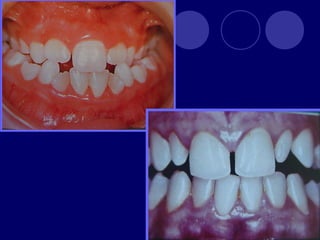

ANOMALÍAS DE TAMAÑO MACRODONCIA:  Generalizada verdadera  Generalizada relativa  De un solo diente

 MICRODONCIA:  Generalizada verdadera Generalizada relativa  De un solo diente

FUSIÓN: unión dedos gérmenes (esmalte,dentina),dos cámaras pulpares, más frecuente en la dentición temporal GEMINACIÓN: tentativa fallida de un germen a dividirse (diente con dos coronas y una sola raíz, un solo conducto)